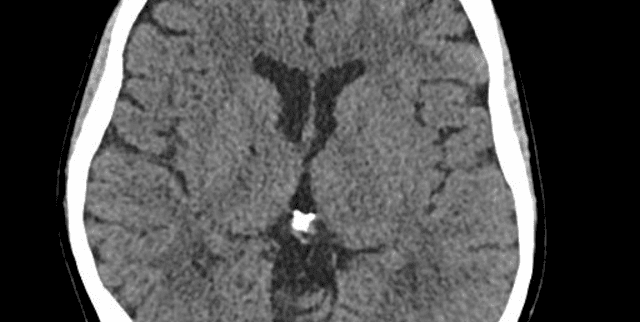

This dataset features Computed Tomography (CT) brain scans, specifically curated for the identification and segmentation of conditions such as cancer, tumors, and aneurysms. It serves as an important resource for research in medical fields, enabling the advancement of automated detection, diagnosis, and classification techniques. Each scan provides a detailed visual representation of a patient's brain.

The dataset comprises 256 distinct CT brain scans, provided in both .jpg and .dcm formats. These images are systematically organised within folders corresponding to the specific brain disease they represent (cancer, tumor, or aneurysm). A accompanying CSV file details each media entry, including links to both image formats and the associated disease type. The 'type' column distribution indicates approximately 35% cancer cases, 32% aneurysm cases, and 32% tumor cases. This dataset is presented as a static collection with no future updates anticipated.

The dataset focuses on detailed CT images of the human brain, specifically covering cases related to cancer, tumors, and aneurysms. It includes brain formations and allows for the detection of abnormalities. General demographic or geographic coverage information is not available within the dataset details.